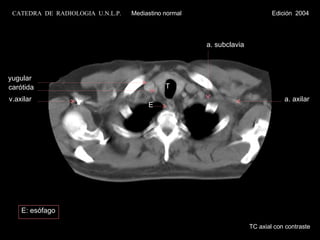

T yugular carótida v.axilar a. subclavia a. axilar E TC axial con contraste E: esófago CATEDRA  DE  RADIOLOGIA  U.N.L.P.   Mediastino normal  Edición  2004

T yugular carótidav.axilar a. subclavia a. axilar E TC axial con contraste E: esófago CATEDRA DE RADIOLOGIA U.N.L.P. Mediastino normal Edición 2004